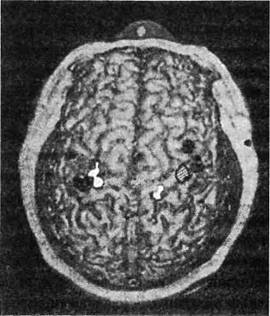

Независимо от того, какая из этих двух теорий — отращивание новых нервных ответвлений или обнаружение подавляемых сигналов — верна, во всем этом есть важная информация для медицины. Целым поколениям студентов-медиков твердили, что триллионы нейронных связей мозга закладываются во время внутриутробного развития и в раннем детстве, в то время как мозг взрослого теряет способность образовывать новые связи. Такое отсутствие пластичности, отсутствие способности восстанавливать или принимать новую форму часто использовалось как оправдание, когда пациентам говорили, почему им следует ожидать лишь очень небольшого восстановления функций после инсульта или травматического повреждения мозга. Наши наблюдения решительно опровергли эту догму, в первый раз показав, что даже основные карты чувствительности мозга взрослого человека могут изменяться на расстоянии в несколько сантиметров. Нам удалось использовать технику сканирования головного мозга, чтобы непосредственно показать правоту нашей теории: мозговые карты Виктора изменились так, как и было предсказано (рис. 1.3).

Вскоре после того, как наши данные были опубликованы, доказательства, подтверждающие и расширяющие эти открытия, стали поступать от многих исследовательских групп. Два итальянских исследователя, Джованни Берлукки и Сальваторе Альоти, выявили, что после ампутации пальца обнаружилась «карта» одного-единствен-

Рис. 1.3. Карта МЭГ (магнитоэнцефалограф) поверхности тела у пациента с ампутированной правой рукой. Заштрихованная область - кисть, черные области -лицо, белые области - верхняя часть руки. Обратите внимание, что область, соответствующая правой кисти (заштрихованная), отсутствует в левом полушарии, но этот участок активируется, когда дотрагиваются до лица или верхней части руки

ного пальца, аккуратно нанесенная на лицо, как и предполагалось. У другого пациента был удален тройничный нерв (чувствительный нерв, иннервирующий лицо), и вскоре на его ладони обнаружилась карта лица, что является точным обращением того, что мы уже наблюдали. Наконец, после ампутации ноги у другого пациента ощущения от пениса чувствовались в фантомной ноге. (Действительно, пациент утверждал, что теперь оргазм распространялся на ногу и из-за этого был «намного сильнее, чем когда-либо».) Такое происходит из-за еще одной странной непоследовательности мозговой карты тела: карта гениталий находится прямо возле карты ноги.